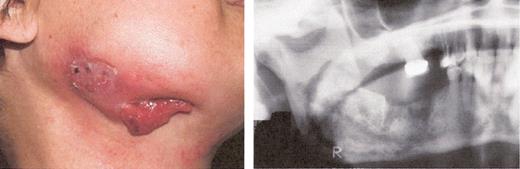

Stage II osteonecrosis of the jaw (ONJ). Patient on zoledronic acid for 18 months.

Stage III osteonecrosis of the jaw (ONJ). Patient on pamidronate for 54 months followed by zoledronate for 18 months.